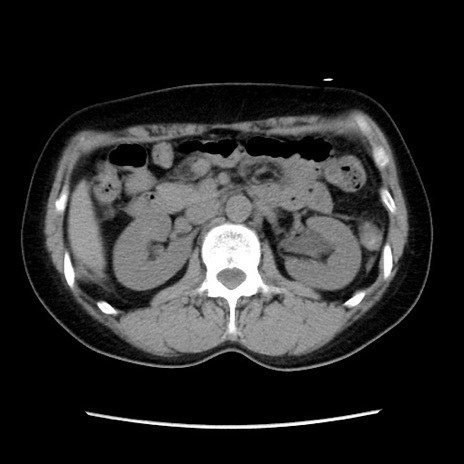

症例10(横断像)

【症例】 50歳代女性

【主訴】 腹痛

【現病歴】前日生レバーを食べた。今朝に排便あり。 昼前に突然発症の腹痛を生じ、当院救急外来を受診した。

【既往歴】 子宮筋腫にてで子宮全摘後

【身体所見】 意識清明、腹部:平坦、軟、下腹部やや左を中心に圧痛・反跳痛あり、筋性防御あり

【データ】WBC 7800、CRP 0.07